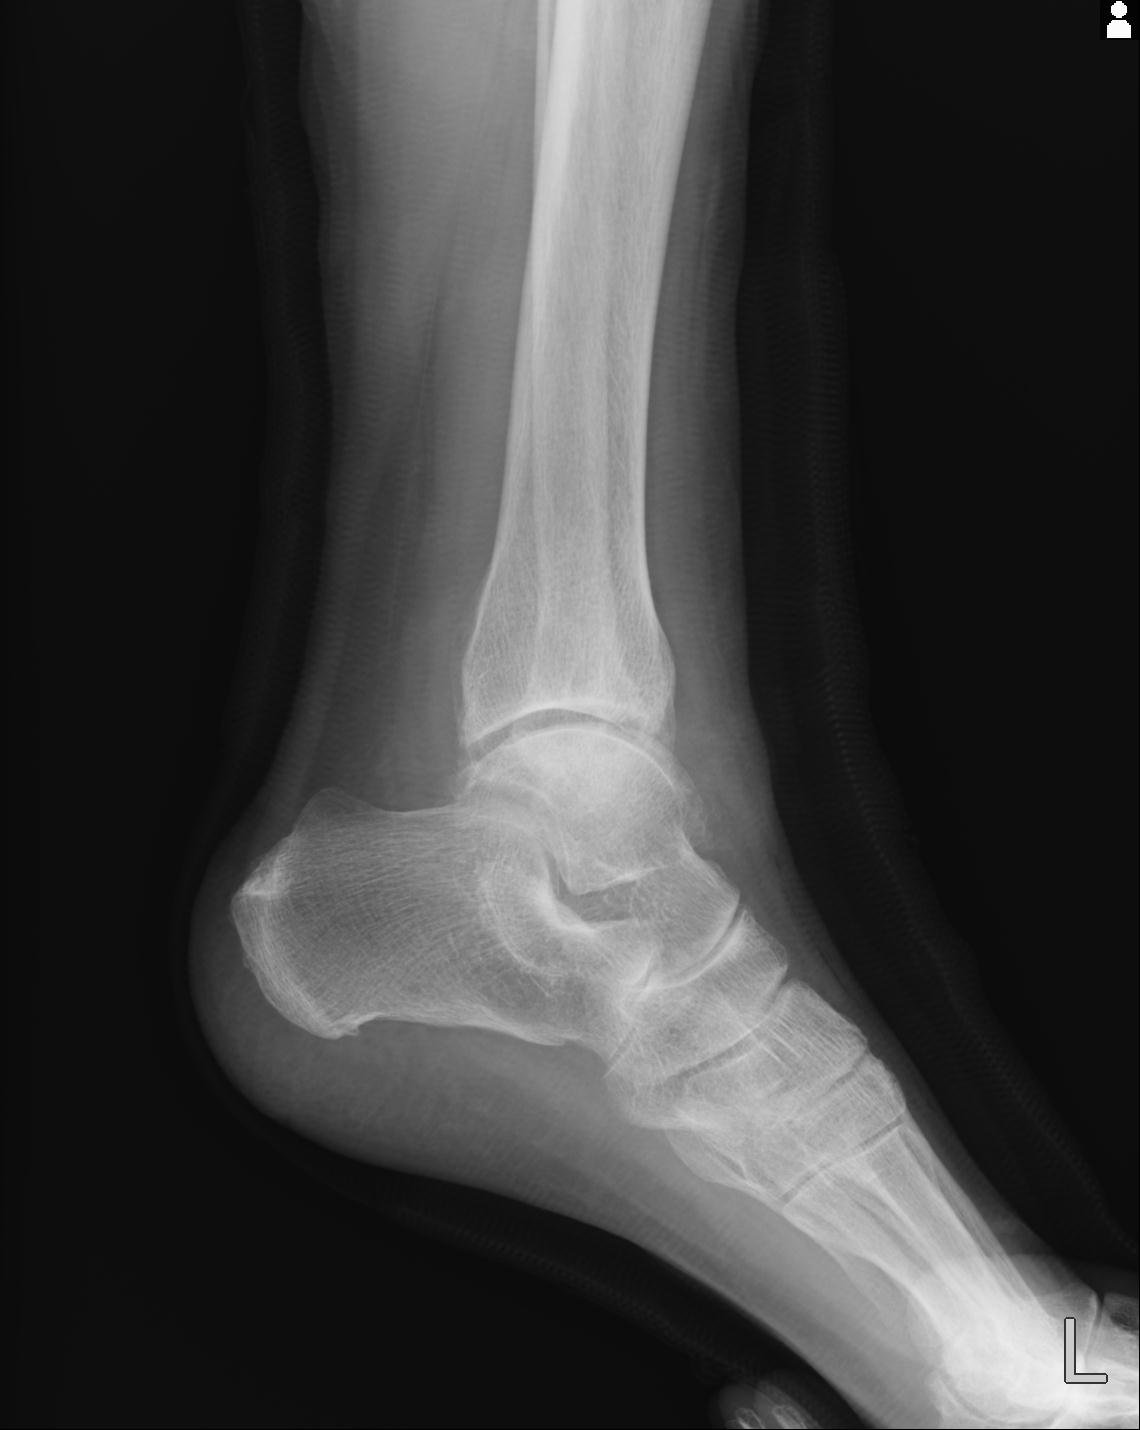

56476 8/28 4R 1/21 2R 左足関節 デジカメ写真 72歳女性 右足関節AS